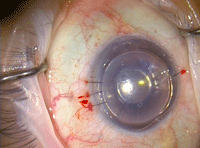

Figura 7. Aspecto final de la cirugía. Se deja la cámara anterior totalmente llena de aire. Con la iridotomía inferior se evita el glaucoma por bloqueo pupilar.